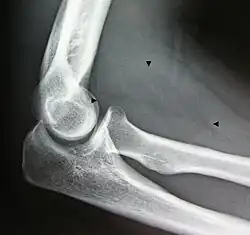

Bone formation may be seen in both lipomas[26] and liposarcomas (a well-differentiated one pictured).

- Resection of an intermuscular lipoma in the elbow region